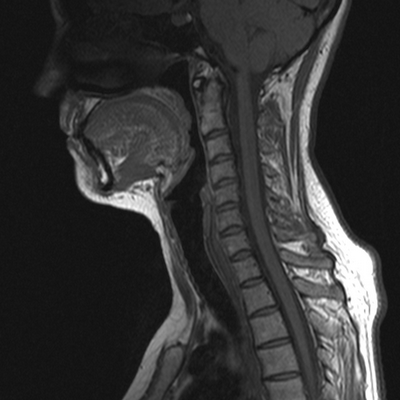

МРТ шеи: оценка спинного мозга (сагиттальная плоскость, Т2 последовательность)

МРТ шейного отдела позвоночника - высокоинформативный неинвазивный способ диагностики, использующий магнитное поле и компьютерную обработку для получения изображений. Преимущества магнитно-резонансного сканирования в сравнении с рентгеновскими методами обследования - отсутствие лучевого воздействия и возможность детализации патологических процессов в мягких тканях: на томограммах видны хрящи, синовии, связки, межпозвонковые диски, спинной мозг, нервы. Если в организме человека нет металлических составляющих или функционирующих устройств с ферромагнитными свойствами, негативные последствия, включая отдаленные, после проведения диагностической процедуры отсутствуют.

При подозрении на опухоль, послеоперационный рубцовый процесс, инфекцию для улучшения визуализационных возможностей используют введение контрастного вещества. Последнее имеет тенденцию накапливаться и очерчивать ткани с аномальными сосудами. Для пациента, который уже перенес вмешательство на шейном отделе позвоночника, усилитель помогает дифференцировать оставшуюся или рецидивирующую опухоль, грыжу диска от рубцовых изменений.